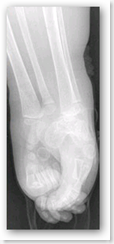

Shiloh is one of only three people in the world known to have a condition called sirenomelia, also known as "Mermaid Syndrome." She was born with her legs fused together, and her parents, Leslie and Elmer Pepin, knew it was possible that their child would be affected by the syndrome before Leslie gave birth.